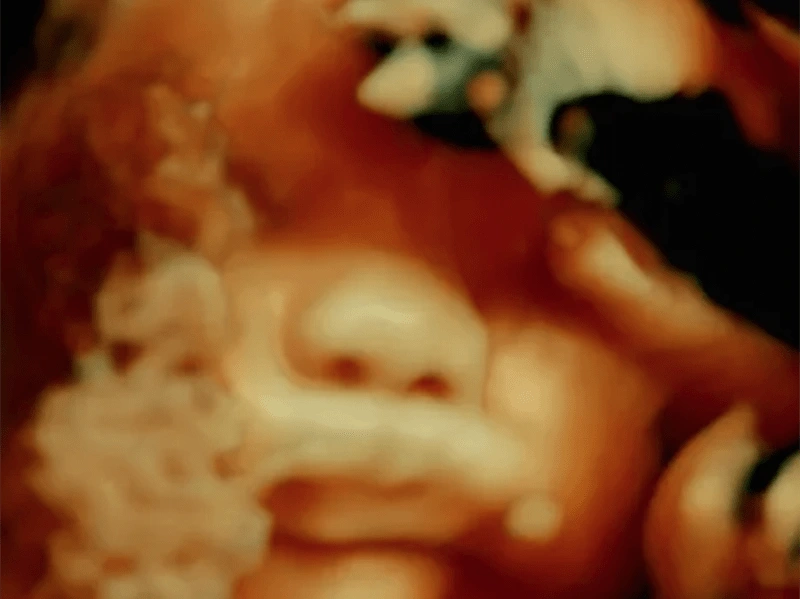

De Humani Corporis Fabrica

Confira detalhes do filme de Lucien Castaing-Taylor e Verena Paravel!